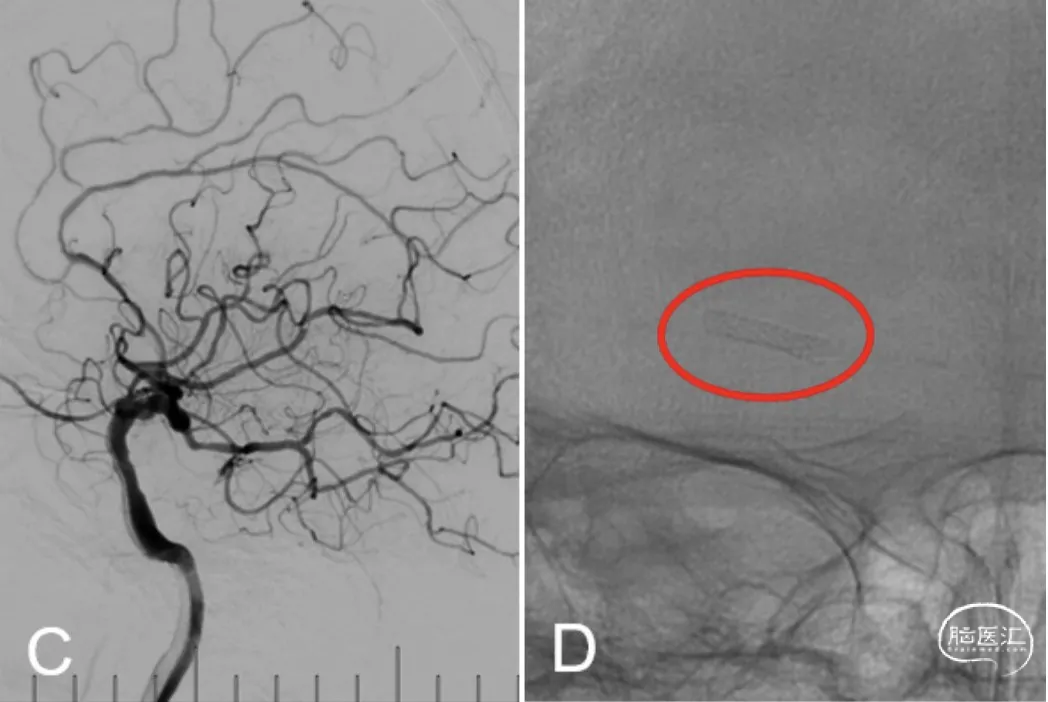

全麻下右股动脉穿刺入路,通过交换技术将7F 90cm长鞘送至右颈内动脉C1段,沿7F长鞘送入5F Navien中间导管至C4段,造影显示右大脑中动脉完全闭塞(图4A,B),造影晚期见大脑前动脉经软脑膜动脉向大脑中动脉供血区代偿供血(图4C,D)。

图4

沿中间导管送入Synchro(0.014″,200cm)微导丝携Echelon-10微导管,路图下小心通过闭塞段至M2段(图5A),撤出微导丝,沿微导管送入Transend(0.014″,300cm)微导丝,撤出微导管,沿微导丝送入Gateway(1.5mm×15mm)球囊,加压扩张后造影显示残余狭窄约50%(图5B),沿微导丝再次送入Gateway(2.0mm×15mm)球囊(图5C),加压扩张后较前好转,残余狭窄约20%(图5D)。

图5

沿微导丝送入Maurora®(2.5mm×12mm)药物涂层支架(图6A),缓慢加压释放支架后造影显示前向血流良好(图6B,C),支架形态满意(图6D),观察10分钟后造影,血流通畅,无急性血栓形成,撤出导管,结束手术。